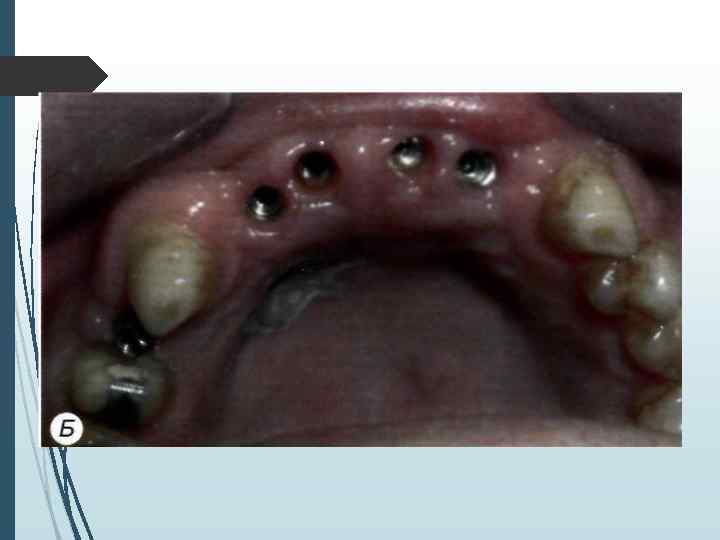

// этап Второй этап операции проводят через 2 3 мес. после установки внутрикостных элементов. Под местной инфи. тьтрапионной анестезией при помощи зонда определяют расположение внутрикостных элементов под слизистой оболочкой. Если из-за значительной ее толщины или нарастания костной ткани на внутрикост-ную часть и заглушку Определить расположение имплантата зондом невозможно, необходимо произвести разрез слизистой оболочки длиной до 10 мм в месте, где должен находиться внутрикостный элемент. Затем, отслаивая слизистую оболочку определяют расположение имплантата визуально. Иссечение слизистой оболочки над внутрикостным элементом производят перфоратором и удаляют иссеченный участок (рис. 11 -5). Выкручивают заглушку. Промывают внутренний резьбовой канал имплантата. Ввинчивают формирователь десневой манжетки, который на ортопедическом этапе. течения заменяют на опорную головку. Если производился разрез, рану зашивают узловыми швами.

А —- иссечение перфоратором слизистой оболочки и надкостницы над внутрикостным элементом; Б — выкручивание винта-заглушки: В — установка формирователя десневой манжетки